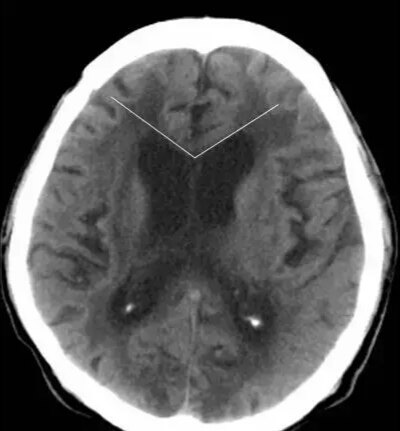

第一招:额角角度

脑萎缩~钝角

脑积水~锐角